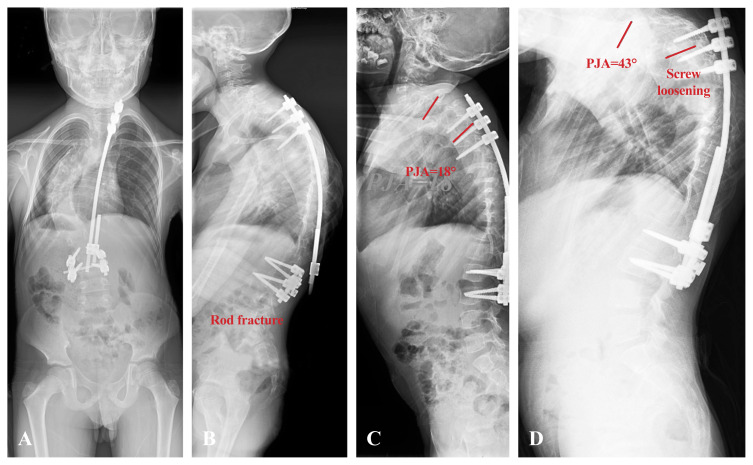

Abstract Image